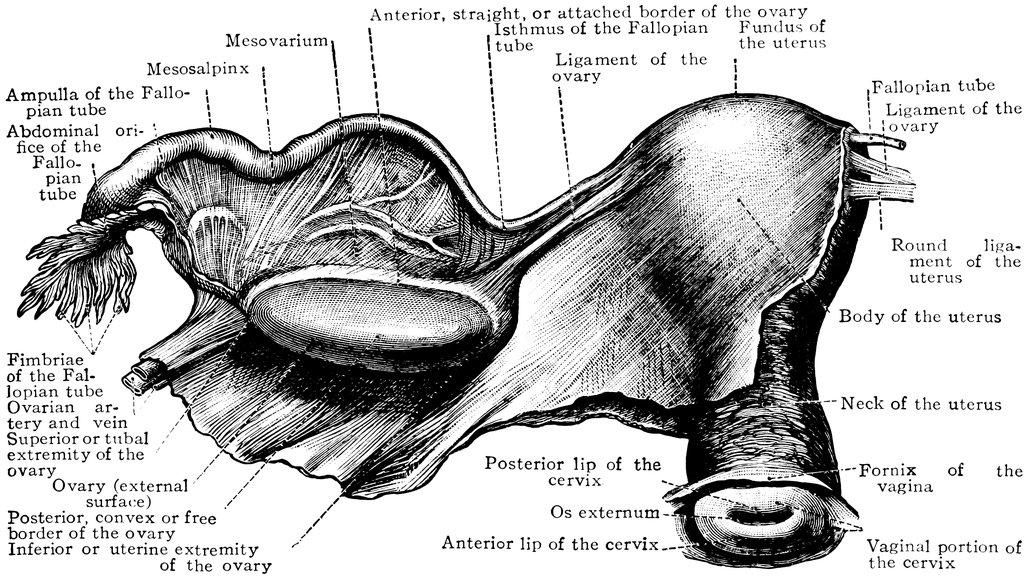

| 50. | The uterus, the left Fallopian tube and the left ovary, etc | 207 |

| 51. | Female internal genital organs in the fully developed state | 208 |